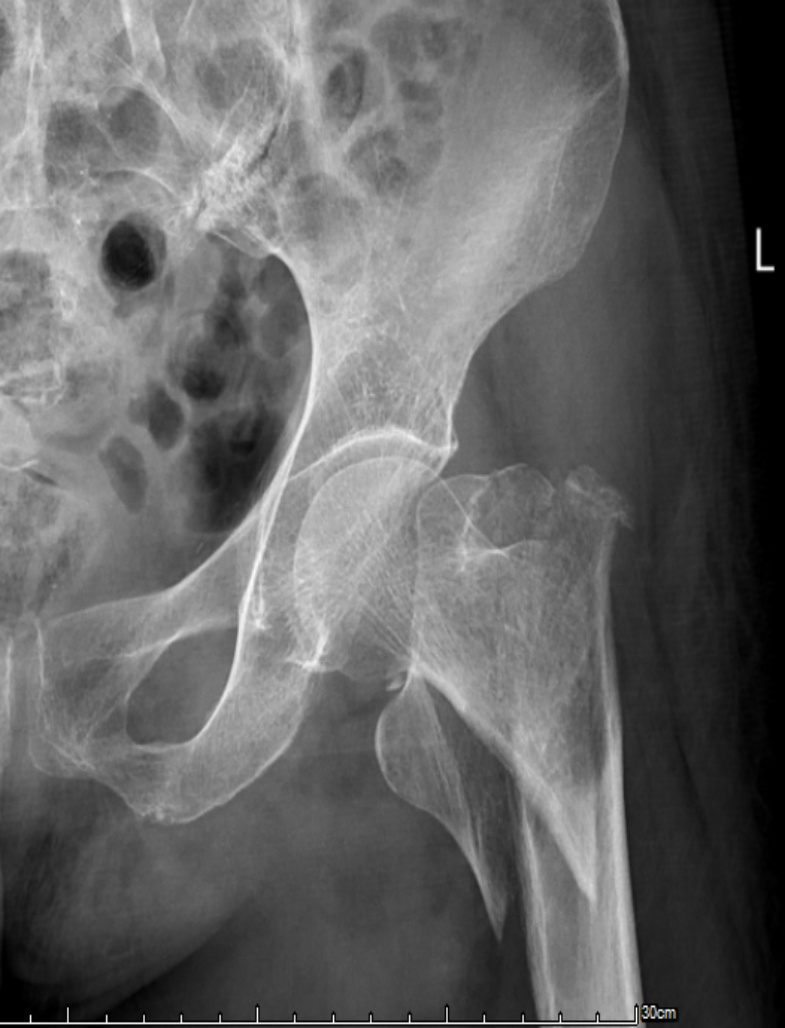

典型病例影像学表现见图1~10。图1为86岁女性右侧股骨转子间骨折(Evans Ⅲ型)患者,术前X线示骨折断端部分错位,术后X线示骨折位置可以及假体位置良好;图2显示了一名81岁男性患者,诊断为左侧股骨转子间骨折,类型为Evans V型,合并股骨干陈旧性骨折。患者接受了生物型加长柄半髋关节置换手术,并进行了股骨近端的钢丝捆扎内固定。术后X线示假体位置良好,股骨近端予钢丝捆扎固定;图3为87岁女性左侧股骨转子间骨折(Evans V型)患者,术后X线示假体位置良好,股骨大小转子骨折位置可,钢丝捆扎固定在位有效;图4为75岁女性左侧股骨转子间骨折(Evans V型)患者,术前X线示左侧股骨转子间骨折PFNA术后、骨折未愈合、内固定断裂。术后假体匹配良好,股骨近端钢丝内固定稳定可靠;图5为75岁男性左侧股骨转子间骨折(Evans IV型)患者,术后股骨大转子出现轻度位移,假体位置正常。图6为87岁男性左侧股骨转子间骨折(Evans V型)患者,给予DAA入路加长柄半髋关节置换,术前X线片,清晰地显示出左侧股骨转子间的骨折情况,术后X线影像,显示股骨的大小转子骨折位置良好,钢丝内固定装置在位稳定,假体位置良好;图7为77岁女性右侧股骨转子间骨折(Evans V型)患者,术前X线片显示右侧股骨转子间存在骨折且股骨大小转子均有累及和移位,术后X线片显示股骨小转子轻度移位,内固定装置位置稳定,假体位置良好;图8为70岁男性左侧股骨转子间骨折(Evans III型)患者,术前的X线片,清晰地显示了左侧股骨转子间的骨折情况,股骨近端髓腔钙化灶,术后假体位置满意;图9为77岁女性右侧股骨转子间骨折(Evans V型)患者,术前X线片,显示右侧股骨转子间及转子下部位骨折情况。术后假体匹配良好;图10为71岁男性右侧股骨颈骨折(Evans IV型)患者,术前X线片,显示右股骨转子间骨折的情况;术后X线表明股骨的大转子和小转子骨折位置保持良好,内固定装置稳固,术后假体位置正常。

Figure 7. A 77-year-old female patient with right intertrochanteric fracture (Evans type V). (a) Before surgery; (b) After surgery

7. 77岁女性右侧粗隆间骨折(Evans V型)患者。(a) 术前;(b) 术后